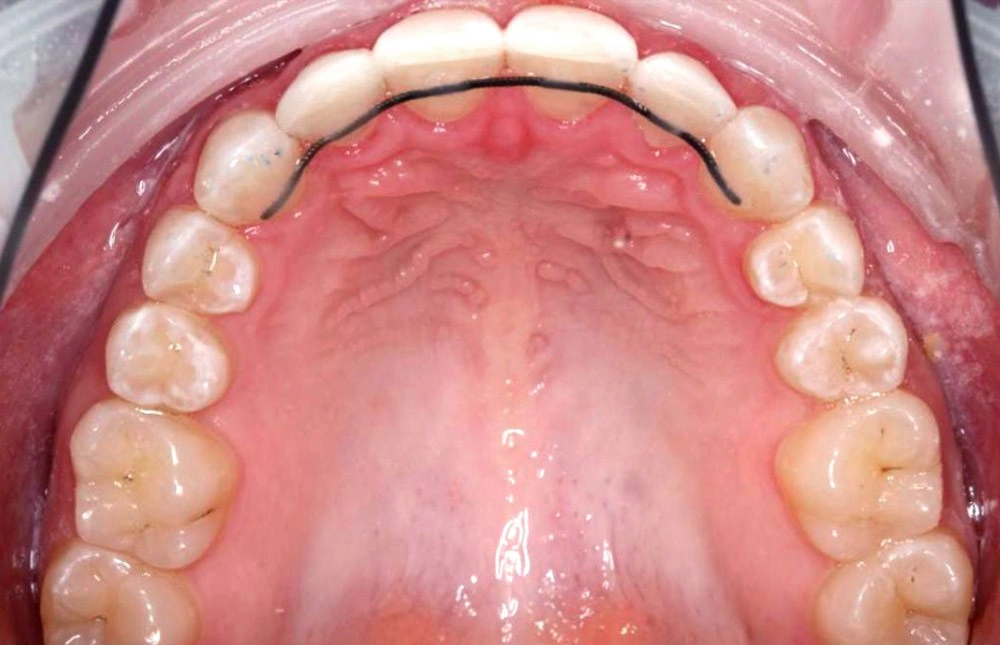

Глубокий прикус - Кейс 5

Эффективность устранения дефекта прикуса посредством элайнеров FlexiLigner.

16

Количество кап НЧ

Количество кап ВЧ

Результаты лечения